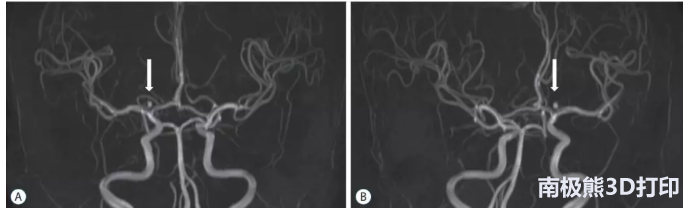

For this study (approved by the Institutional Review Board of Pusan National University Hospital), 20 patients with unruptured intracranial aneurysms were divided into two groups. 10 patients passed3D printingThe model (created on Nobel 1.0A with PLA) was educated, while another 10 patients received traditional computed tomography angiography (CTA).

A doctor is not only responsible for all 20 operations, but also responsible for explaining the procedure at hand, eliminating any concerns about prejudice or procedural differences in the educational process. The model is used as a companion to preoperative consent, and the study proved to be helpful in gaining a clear understanding of the patient’s understanding of the new technological process.After reviewing the results of the study, the author found that the data showed3D printingThe model significantly improves the process because the patient has a better understanding of what is happening and at the same time has a higher degree of satisfaction with the operation.